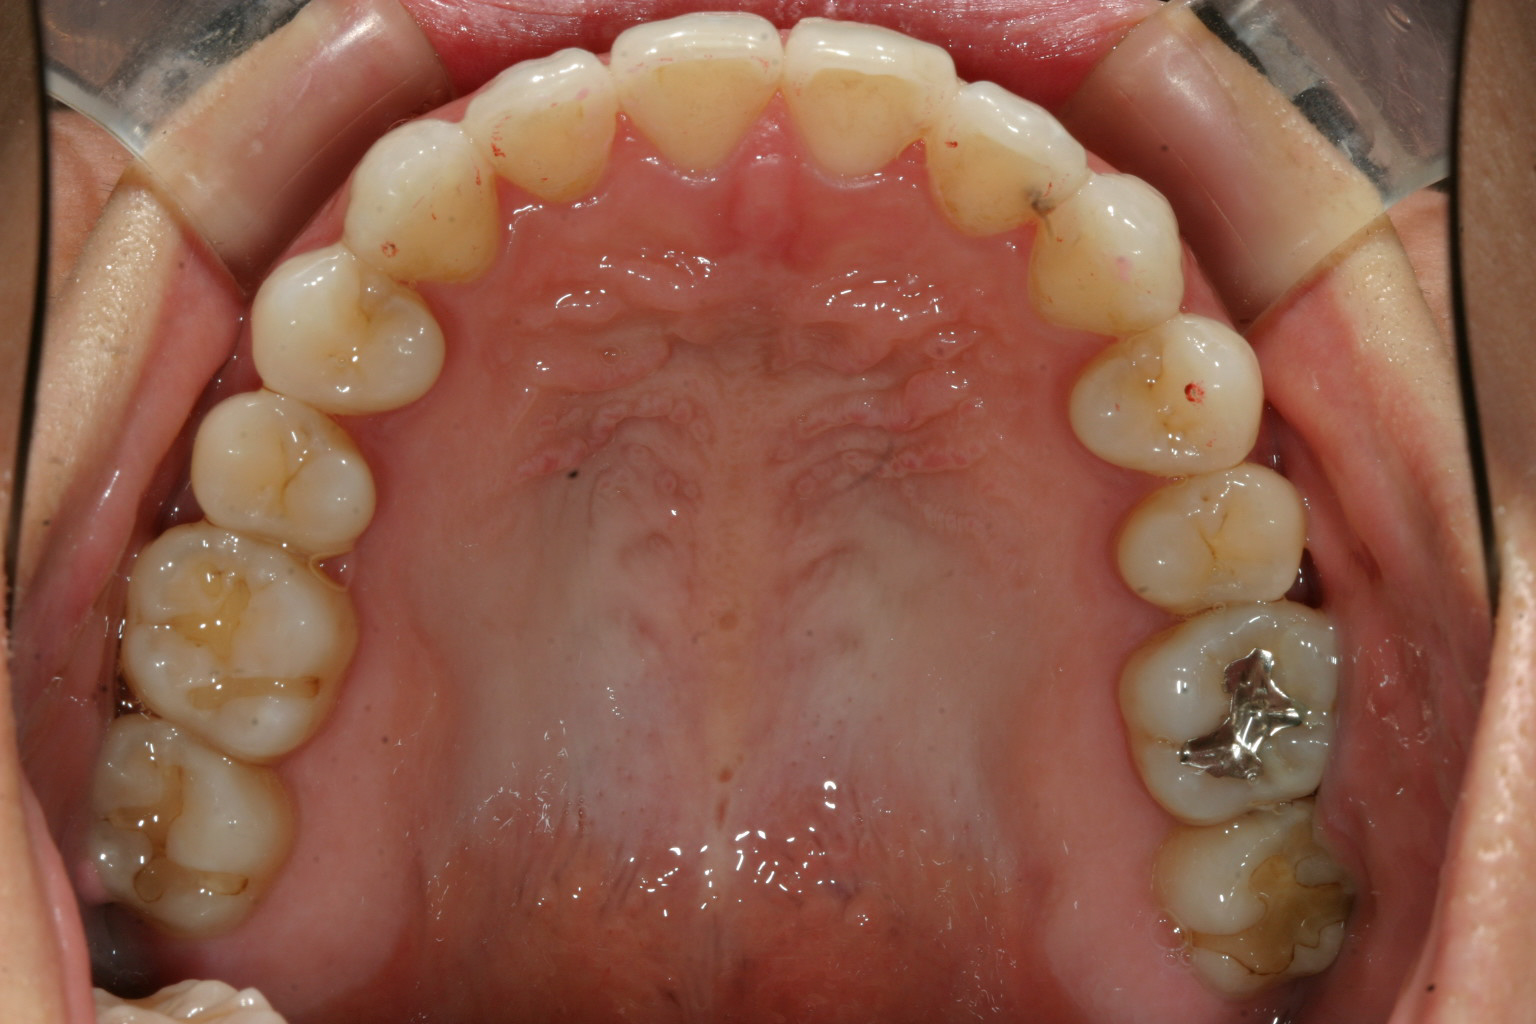

上顎綺麗に並びました。

下顎もバッチリです。

綺麗な被蓋関係に改善されました。

今回の症例ではインビザライン矯正で得意とする手法でIPRって事メインに行いました。IPRと言う方法は上下の歯と歯の間を少し削り上下の歯のバランスを変えると言う方法です。(最大でも隙間に0.5mm程です。)

下顎の歯の隙間を沢山削り上顎は少し削って全体的にアーチを締め付ける事により下顎のアーチを小さくして上顎より内方に入れ、上顎前歯を少し下に下げれば綺麗な被蓋関係が出来上がります。